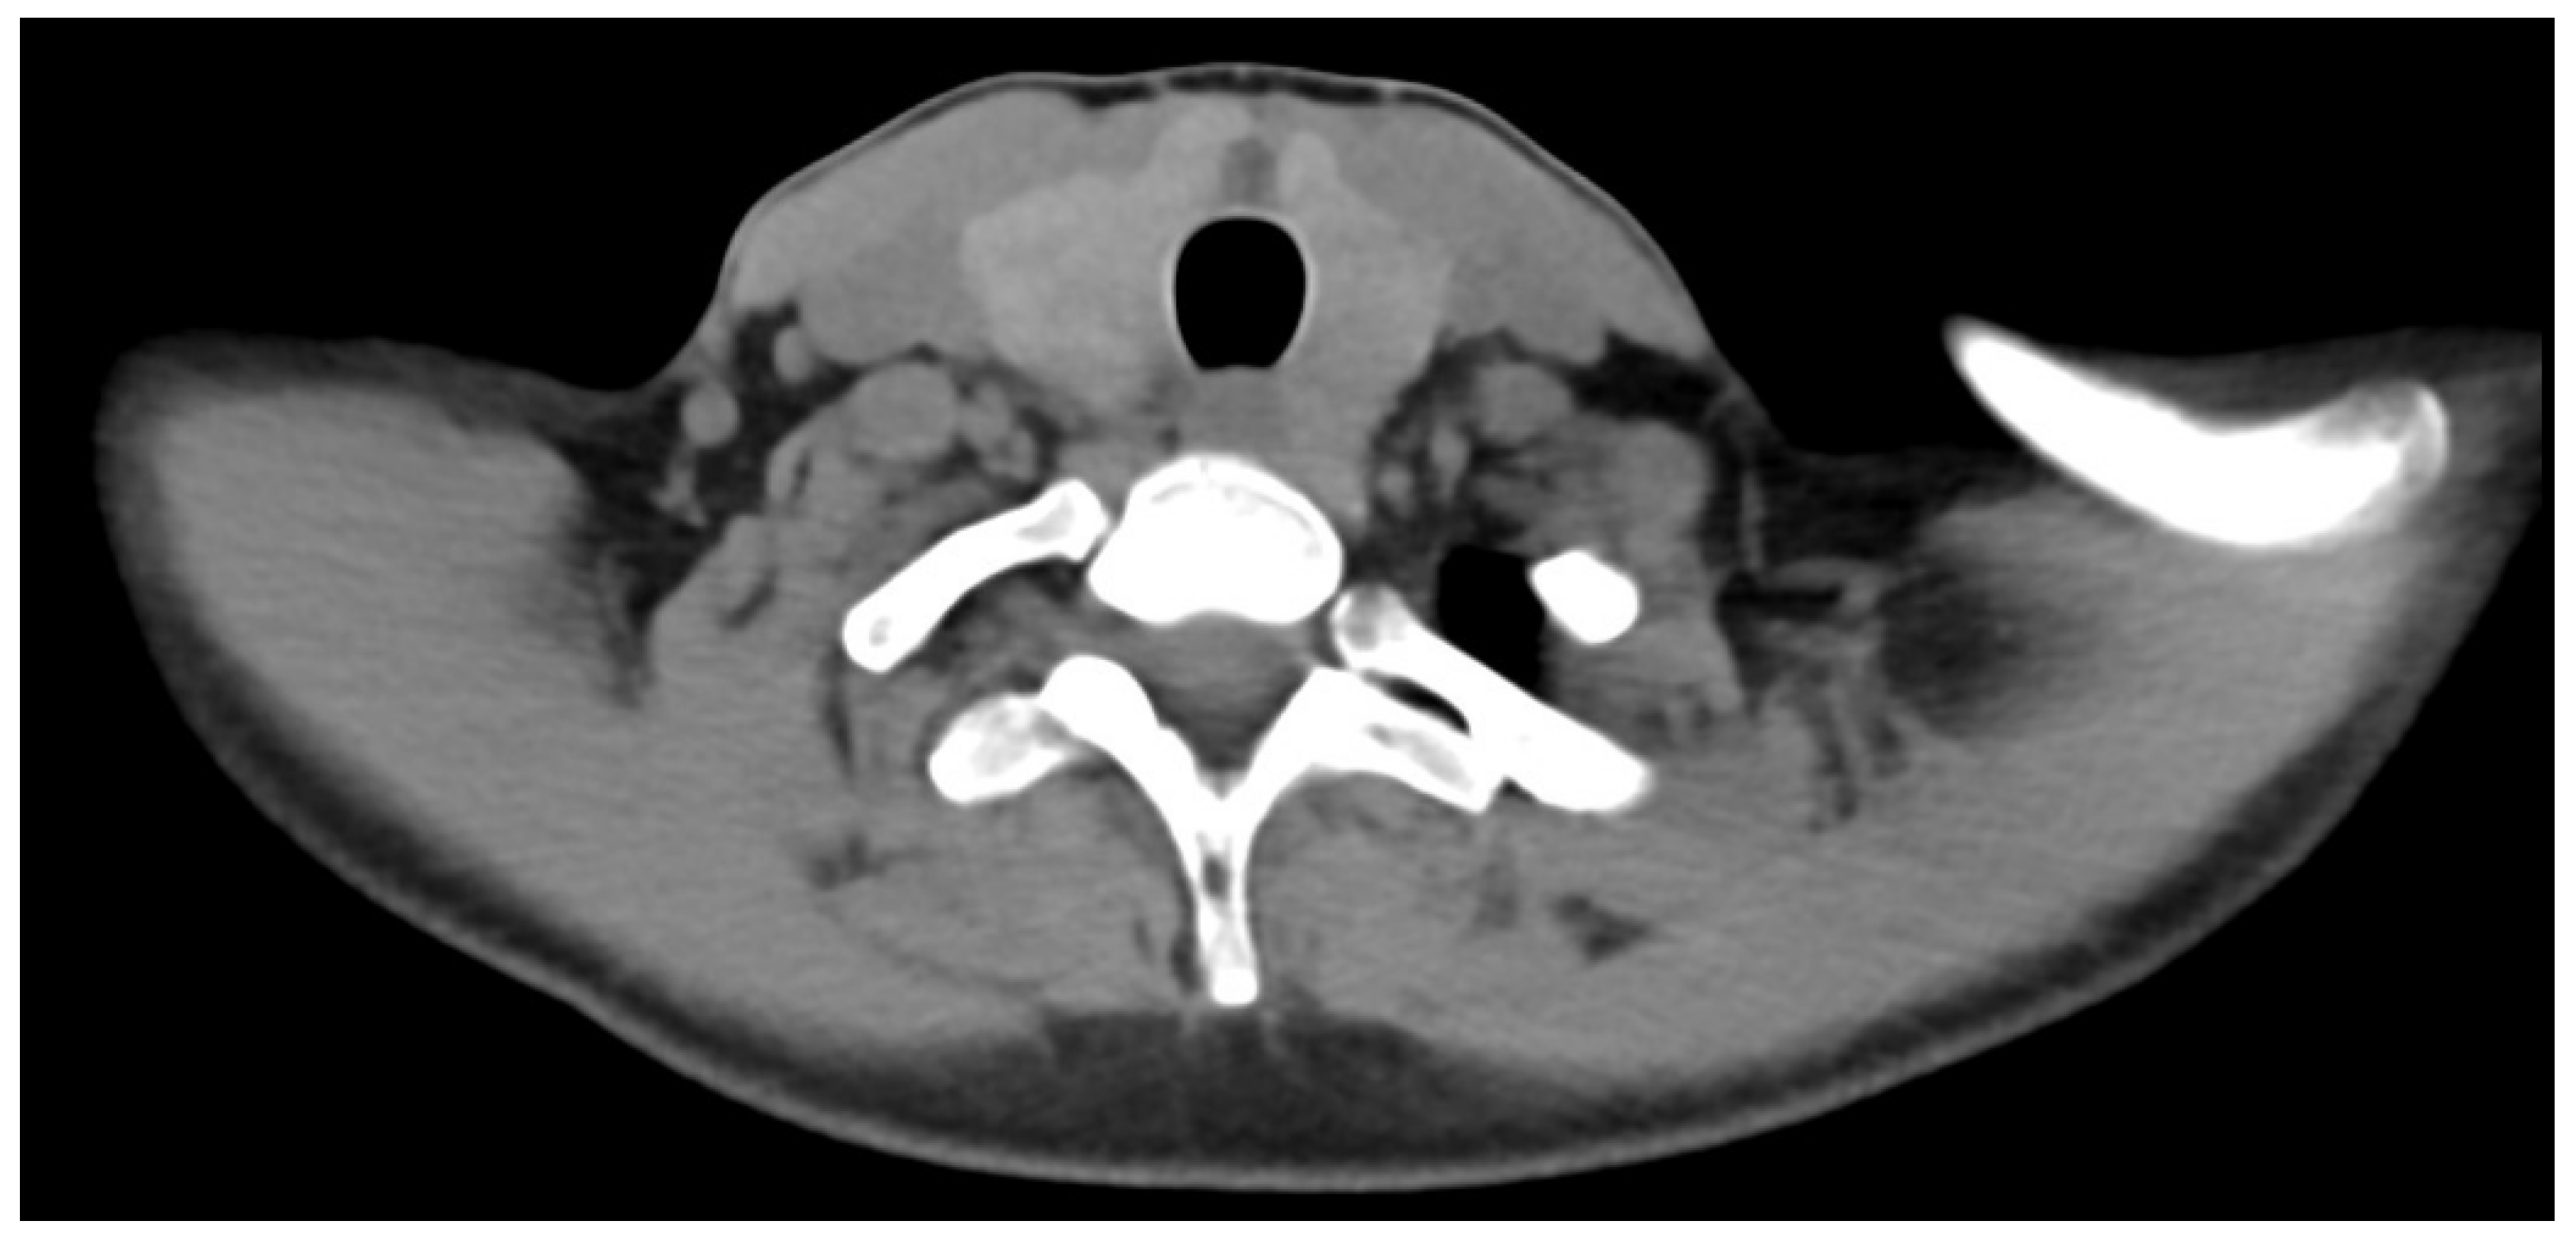

2. Case Report